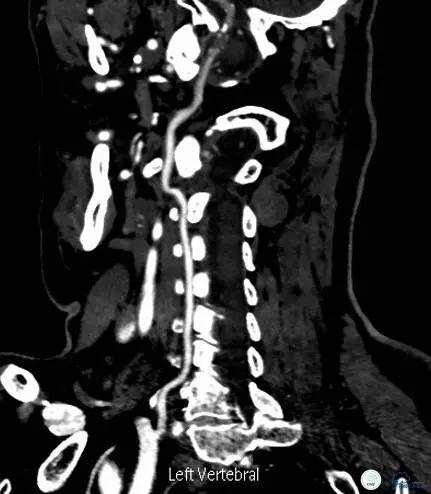

头颈部CTA(图3-6):双侧椎动脉远端及基底动脉近端混合斑块、管腔中-重度狭窄,双侧大脑后动脉纤细。

图3

图4

图5

图6